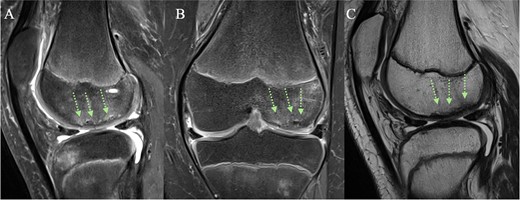

Postoperatively, no weight-bearing was permitted for 6 weeks, followed by two additional weeks of partial weight-bearing. The knee was immobilized in extension for the initial 2 weeks, after which knee flexion up to 60° was permitted during weeks 2–4, and up to 90° during weeks 4–6. Subsequently, knee flexion was encouraged. The postoperative rehabilitation program was overseen by a physiotherapist to ensure adherence and proper progression. Four months post-surgery, MRI examination revealed complete healing, despite minor subchondral abnormalities (Fig. 4). The patient was able to walk independently without experiencing pain; however, a mild flexion deficit of 25 degrees was present, which will be monitored for improvement.

(A + C) Sagittal and (B) coronal MRI views 4 months post-operatively. The arrows indicate healing of the chondral fracture, although some minor subchondral abnormalities are present.